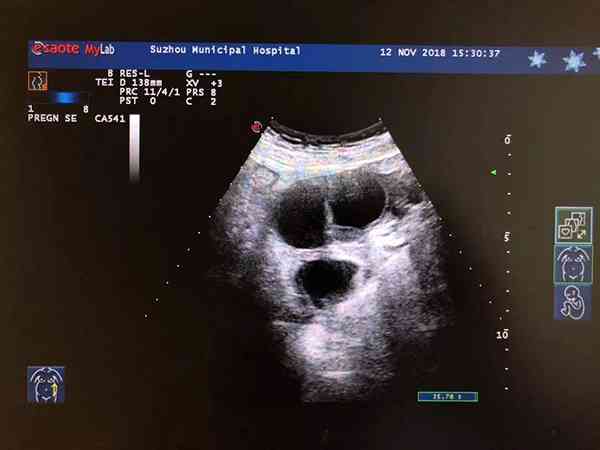

2017年做過巧克力囊腫腹腔鏡剝離手術,半年後復發。19年懷孕,20年生孩子。右側囊腫一直存在,之後沒有管巧囊,因為沒有啥症狀,今年4月份到醫院檢查發現巧囊已經長到6公分了,本來打算這個月去做手術給剝離的,結果去醫院檢查發現巧囊消失了,我也沒做手術啊,請問這是破裂了嗎?巧克力囊腫6公分如果沒做手術突然消失了那麼較大概率是診斷出錯,把生理性囊腫誤診成了巧囊,因為巧囊一般很難自行消失。但也不排除可能還是破裂了,這種情況囊腫內液流出來會刺激到盆腔,會引起會劇烈腹痛、肛門墜、脹壓痛及反跳痛等症狀。除此之外,還有可能是服用藥物使巧囊吸收消失的。

卵巢巧克力囊腫是子宮內膜異位症的一種病變,患病會出現同房疼痛、月經失調、難以懷孕等巧克力囊腫症狀。該疾病是很難治癒的,其一般需要藥物治療+手術治療才行,如果在沒做手術的前提下發現巧克力囊腫6公分突然消失了,可能是以下原因導致的:

將生理性囊腫診斷成了巧克力囊腫,女性排卵之後,卵巢區域性會形成黃體,少量的出血加上壓力增大,就會出現黃體囊腫,但該囊腫在臨床上也不會引起相應的症狀,在月經乾淨後就會縮小消失。

6公分的巧囊突然消失,也可能是囊腫破裂了,但這種情況女性會有明顯感知,因為巧囊破裂會導致女性出現急腹痛,需要到醫院進行處理治療才行。

對於囊腫較小的情況,突然消失,有可能還是因為藥物治療使囊腫自行吸收導致的,但是對於6公分的巧囊來說,該情況發生的概率是較小的。